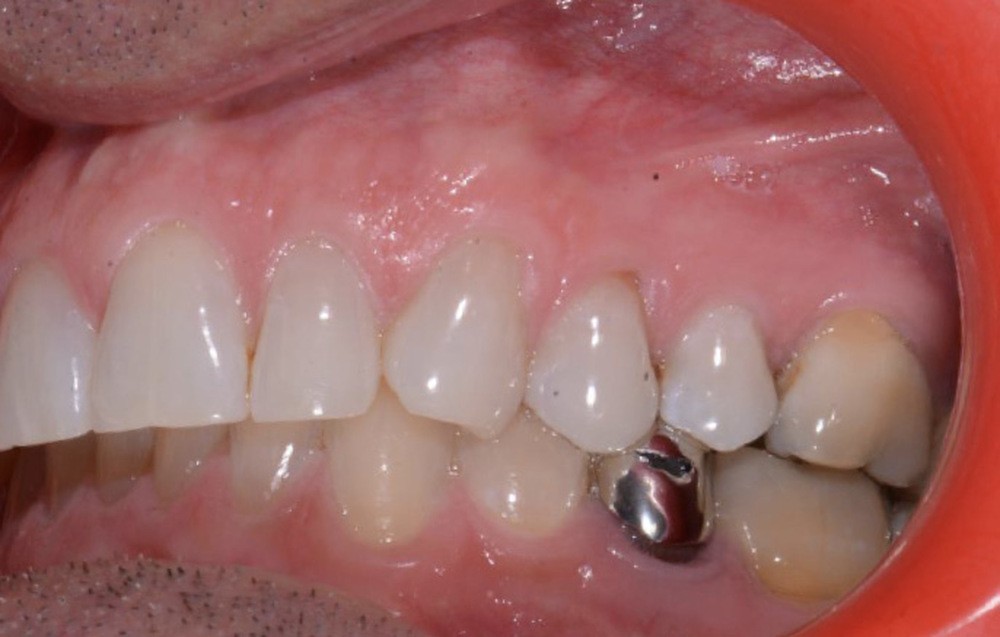

Plan de traitement

(fig. 4 à 10)

Le plan de traitement établi conjointement avec son chirurgien-dentiste traitant consiste à réaliser un alignement dentaire mandibulaire et à réaliser des extractions de 16 et 15 pour un remplacement par prothèse implanto-portée.

La durée orthodontique prévue est de neuf mois, avec comme contrainte principale l’absence de possibilités de modification des formes d’arcades.

Le gain de place se fera par des réductions interproximales sur la zone incisivo-canine mandibulaire.

Il est décidé de ne pas redresser la 43 complètement afin de ne pas entraîner d’interférences occlusales.

Un accompagnement par des meulages occlusaux est réalisé.